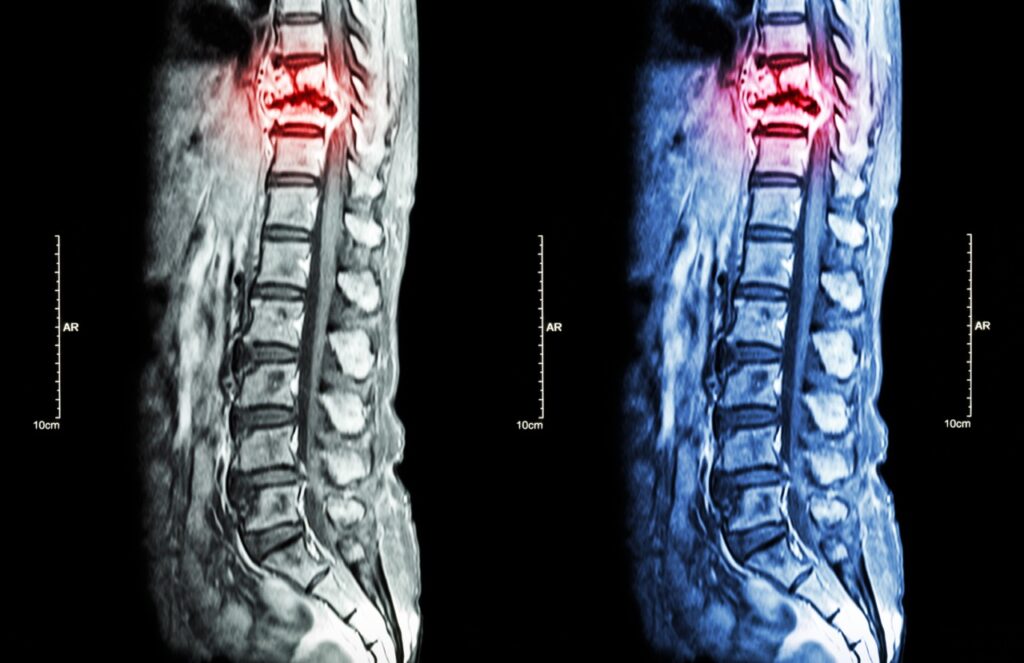

How a Spine MRI Can Help Diagnose Your Back Pain

Spine MRI for Back Pain: A Guide to Accurate Diagnosis Back pain can turn simple tasks into daily struggles. You wake up stiff, struggle to tie your shoes, and avoid activities you once enjoyed. When pain persists for weeks or months, you need answers about what’s causing your discomfort. A spine MRI for back pain […]

Spine MRI in Pembroke Pines: Fast Diagnosis for Back & Neck Pain

Fast Relief from Back and Neck Pain with a Spine MRI in Pembroke Pines Back and neck pain can control your entire day. You wake up stiff, struggle through work, and go to bed aching. When pain becomes a constant companion, you need answers fast. A spine MRI in Pembroke Pines provides the detailed imaging […]